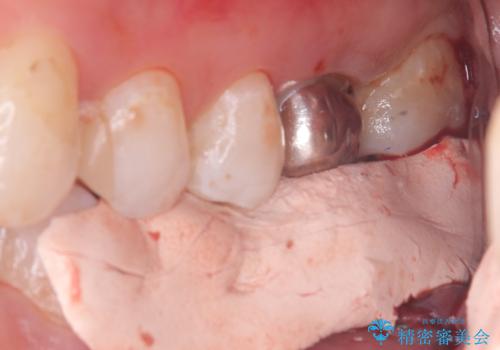

左下6番目の歯の周りに大きく透過像を認め、再根管治療後の予後が良くない可能性が大きく当院でも抜歯適用歯と説明しました。欠損部に対しインプラント治療や歯牙移植(左下の親知らずの移植)、ブリッジを提案し、歯牙移植を行うこととなりました。

保存が難しい左下6番目の歯を抜歯し、左下8番目の歯(親知らず)を抜歯窩に移植しました。歯牙移植後の動揺防止のため暫間固定を行っています。

また移植後2週間経過時点で根管処置が必要となります。